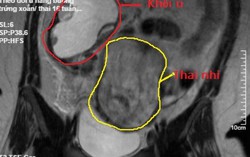

Phát hiện u nang buồng trứng xoắn hoại tử sắp vỡ khi mang thai 16 tuần

15:49 17/03/2019Các bác sĩ phát hiện bệnh nhân có khối u buồng trứng phải xoắn, kích thước lớn và có dấu hiệu hoại tử sắp vỡ đe dọa tính mạng mẹ con thai phụ nên chỉ định nội soi cấp cứu.